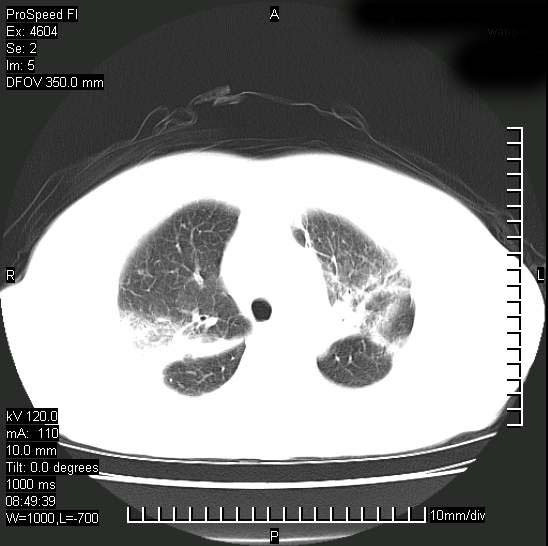

标题: CT15528:女性,79岁,近几日晚上高热,39度,仍咳少量血

十几年前曾患肺结核,一周前突咳血约100ml,中性粒细胞稍高,诊断两上肺陈旧结核,下肺炎症,给予抗炎治疗,近几日晚上高热,39度,仍咳少量血,4天前ct及今天ct上传。

[face=黑体]8月30日[/face]

支持陈旧性肺结核并两下肺感染,两侧胸腔积液。

支持  结核ban感染,节段性肺不张,支气管内膜结核可能

继发性结核感染加重。左侧合并有支气管内膜结核。

1)两肺结核并感染。2)不排除左肺上叶中央型肺癌并阻塞性肺炎、肺不张可能;建议行纤支镜检查。3)右肺门及纵隔淋巴结肿大。4)双侧胸腔积液。

陈旧性肺结核及左下肺不张,咯血后肺部感染,双胸腔积液,高热可能与痰液引流不畅有关。